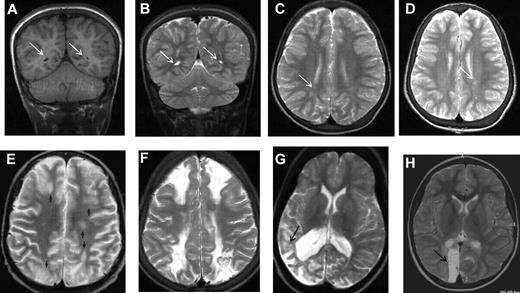

MRI in sickle cell disease. Coronal T1-weighted MRI (A,E) and axial T2-weighted MRI (B-D,F-H) in patients with homozygous SCA. (A-C) Normal MRI in a 19-year-old man with homozygous SCA. (D) Three years later, there is no change. (E-G) Silent infarction (arrows) in the frontal white matter and basal ganglia in a 15-year-old girl with cognitive problems affecting school performance but no acute neurologic presentation. (H) Three years later she has further infarcts with evidence of mild generalized atrophy and had a transient right hemiparesis as well as developing signs of a diplegia.

The largest longitudinal cohort study to address the prevalence and incidence of SCI in children with SCA was the CSSCD, an observational study of children identified as infants and followed closely over the subsequent decade, which used MRI of the brain to detect abnormally increased T2-weighted signal intensity on multiple views (Figures 1 and 2) in children without current focal neurologic deficits as assessed by a hematologist. Previous neurologic history other than seizures, for example, coma, dizziness, ataxia, or transient focal weakness, was not explored. Hematologists may have discounted subtle neurologic findings that may have classified as abnormal and suggesting a prior overt stroke if reviewed by neurologists.6 The more precise definition used by Casella et al7 in The Silent Cerebral Infarct Trial (SIT Trial)7,8 included a MRI lesion measuring at least 3 mm in greatest linear dimension, visible in at least 2 planes of T2-weighted images (axial and coronal; Figure 2B-C). The SIT Trial definition excluded prior seizures and required no current focal neurologic deficit that could be explained by the anatomic location of the presumed SCI. Thus, individuals could have a focal neurologic examination, for example, compatible with a peripheral neuropathy, but would still meet the definition of SCI if the location of the infarct would not account for the neurologic deficit.

As part of the protocol for the observational CSSCD cohort, the leadership group added serial surveillance MRI scans of the brain of children beginning at 6 years of age. A total of 266 children with SCA hemoglobin SS (HbSS) completed both a MRI of the brain and a battery of age-appropriate tests of cognitive function. The average age at initial scan was 8.3 years with each child having at least 1 follow-up scan at a mean of 12.1 years of age. The mean interval between first and follow-up studies was ∼ 2 years. In this cohort, the prevalence of SCI at baseline was 21.2%.15 SCIs commonly differ in size and location compared with overt strokes. Whereas overt strokes are typically located in both cortex and deep white matter,16 SCI in the CSSCD typically occurred in the deep white matter of the frontal (81%; Figure 1E-F) or parietal (45%) lobes (Figure 2A-D), followed in frequency by the basal ganglia (Figure 1G-H) or thalamus (16%) and the temporal lobes (9%).15 Similar observations were reported for an unselected cohort of 132 children with SCA in Créteil, France undergoing brain MRI as part of routine medical care2 and in other studies.4,5,17,18 SCI in SCA are typically smaller in size compared with overt strokes. In the CSSCD participants, 83% of the children with overt strokes, but only 16% of those with SCI, had lesions that were at least 1.5 cm.15